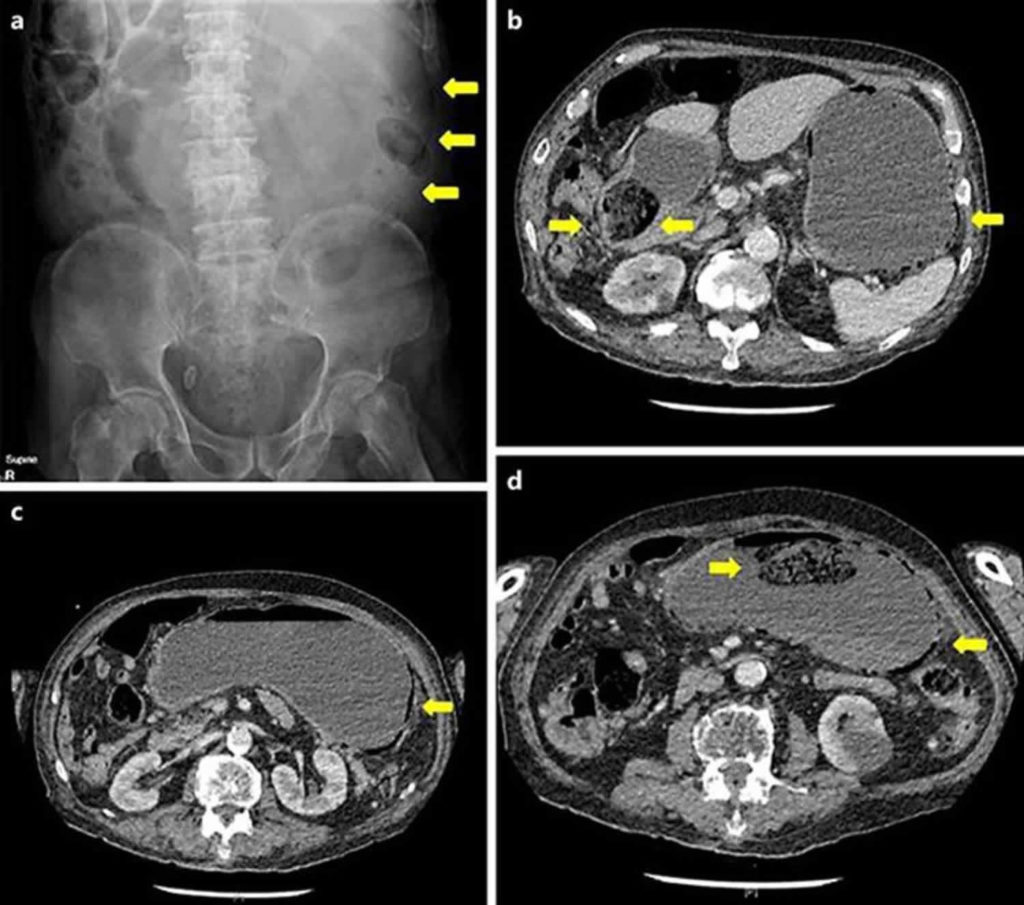

From www.semanticscholar.org

Figure 1 from Migration of gastric bezoars leading to secondary ileus How Are Bezoars Removed Learn how they can be dissolved or. During endoscopy, doctors sometimes use forceps, a laser, or other instruments to break bezoars into pieces so that they can pass through or be. A bezoar forms when certain substances or materials accumulate and clump together in the gi tract, creating a solid mass. The bezoar may need to be surgically removed, especially. How Are Bezoars Removed.

From www.researchgate.net

(A) Detection of a gastric bezoar of approximately 6 cm by How Are Bezoars Removed The bezoar may need to be surgically removed, especially if it is large. A bezoar forms when certain substances or materials accumulate and clump together in the gi tract, creating a solid mass. The exact process of bezoar formation can vary depending on the. The bezoar may need to be surgically removed, especially if it is large. In some cases,. How Are Bezoars Removed.